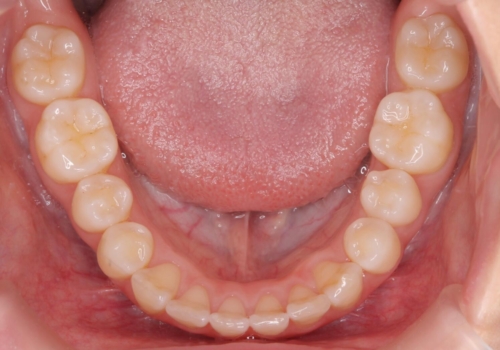

- 前歯が出ていることを主訴に来院。

歯を抜かずにマウスピース矯正をご希望でした。

歯と歯の間をわずかに削り、歯並びを少し横に拡大して並べました。

奥にすき間がなかったため後ろには下げていません。

沢山ひっこめるには4本抜歯でワイヤーの選択肢もありましたが、抜かないでできる範囲をご希望されました。

とがった形の歯列を整えるだけでもだいぶ印象は変わると思います。

今回歯列を広げた結果、上顎犬歯の歯肉は多少退縮しています。